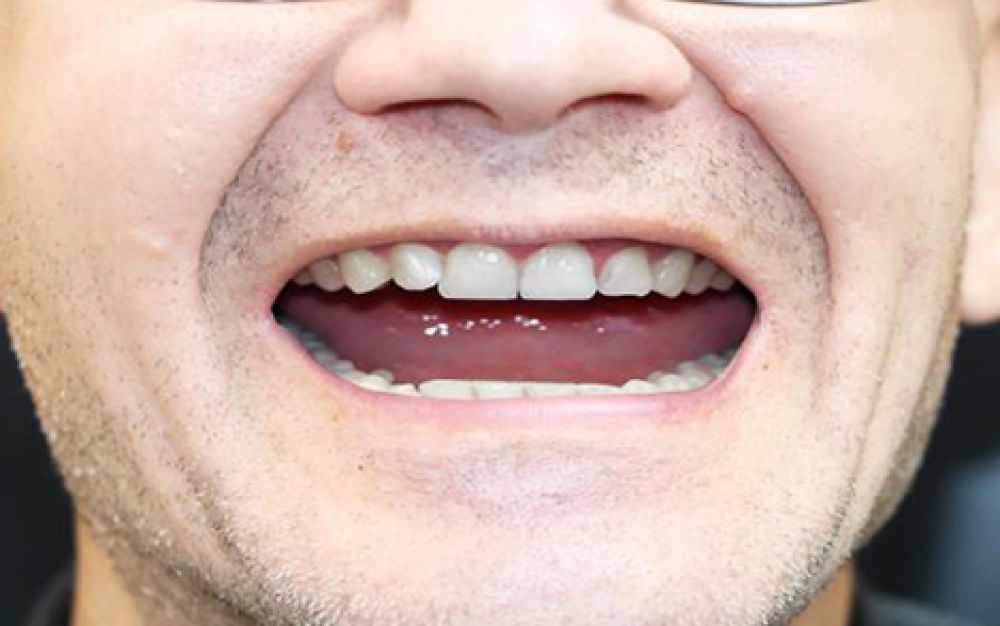

Before

After